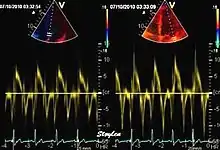

Colour tissue Doppler

Colour tissue Doppler traces from a normal subject Left: traces from the septum and mitral ring. The similarities of the curve shape to spectral Doppler is evident. Right: multiple traces from sites along the septum. The decreasing velocities from base to apex is evident.

Unlike spectral Doppler, colour tissue Doppler samples velocities from all points of the sector, by shooting two pulses successively, and calculating the velocity from the phase shift between them by autocorrelation. The calculation is slightly different from the true Doppler effect, but the result becomes identical. This results in a single velocity value per sample volume. The result is a velocity field of (nearly) simultaneous velocity vectors towards the probe. The advantage of colour Doppler over spectral Doppler is that all velocities can be sampled simultaneously. The disadvantage is that if there is clutter noise (stationary reverberations), the stationary echoes will be integrated in the velocity calculation, resulting in an under estimate. As pulsed wave Doppler are displayed as a spectrum, the colour Doppler values will correspond to the mean of the spectrum (in the absence of clutter), giving slightly lower values. In the HUNT study, the difference in peak systolic values were about 1.5 cm/s.[26]

The local velocities are not the result of the local function, as segments are moved by the action of neighbouring segments. Thus the velocity differences velocity gradient are the main measure of regional contraction, and has become the most important employment of colour tissue Doppler, in the method of strain rate imaging.[27]